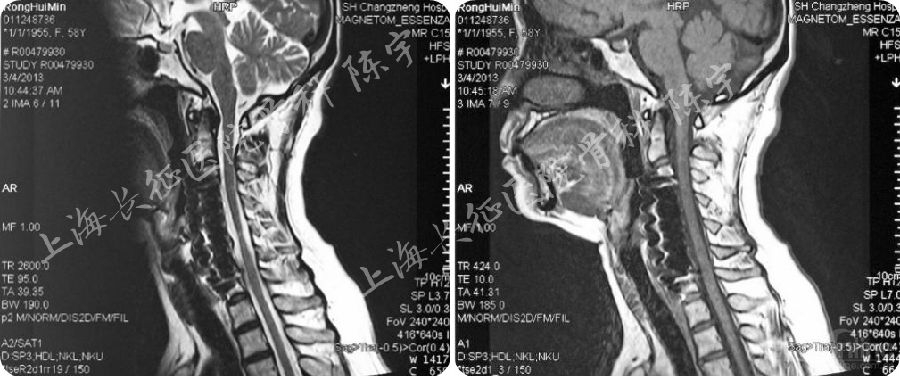

术后影像学检查(图2):

(1) X线:显示颈前路C4-6椎体次全切除减压钛网植骨融合术;

(2) MRI:显示术后脊髓减压充分,脊髓形态完全恢复;

(3) CT: 显示后纵韧带骨化物完全切除,硬膜囊骨化保留并向前漂移。